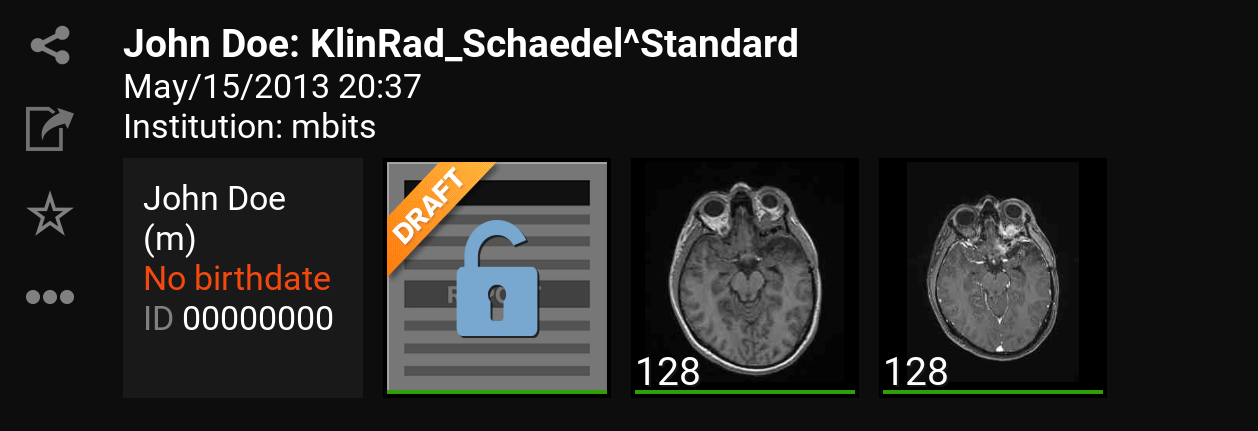

9.1. Inbox

The (Inbox) will be opened after logging in. With this you can browse and select the wanted DICOM files, which are enabled for you through the server. Thus you can see all files on the mRay server on which you have access rights.

Shows information or rather missing information and meta data from a patient.

-

Shows an overview of the contained series in a study. By clicking a study you will get to the series selection (see Series selection). The green marker under any thumbnail indicates that the image data is stored locally and offline available.

9.2. Series selection

-

Back: return to the inbox.

-

Datasets: Enumeration of all recorded images of the study of a patient.

By clicking a series it will be downloaded (if it’s not already downloaded) and opened for viewing.